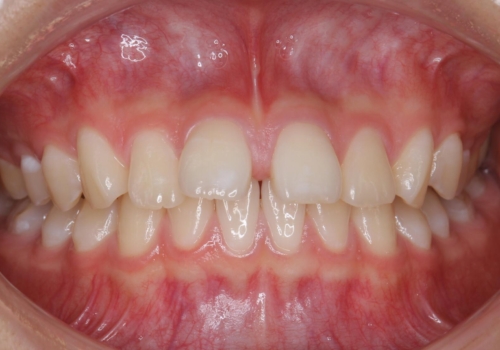

前歯のすき間が気になる 部分矯正で

- 前歯のすき間を気にして来院。

全体矯正ではなく部分矯正で治療することになりました。

その代わり、すき間をすべて閉じるのは難しく、両脇の目立たないところに集めて治療終了しています。